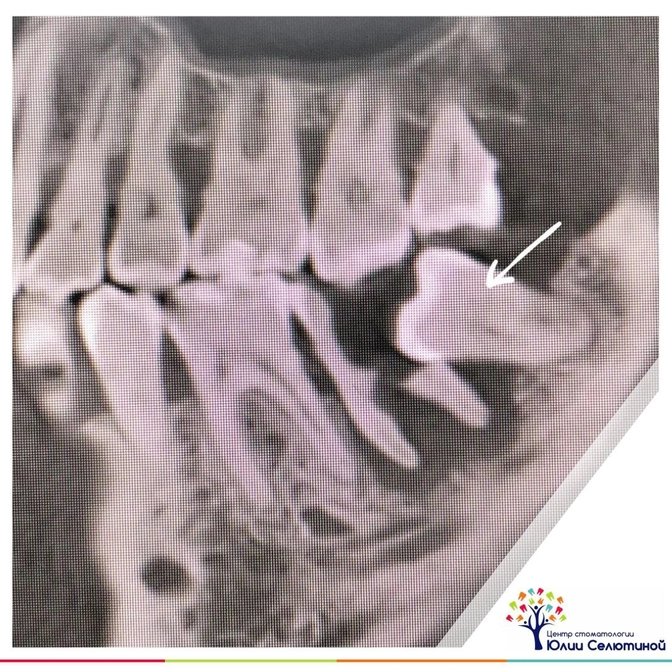

Сильно так упирается, даже не по касательной.

Этим он спровоцировал разрушение "семерки", да такое, что восстановить ее уже не удастся.

Оба зуба пришлось удалить.